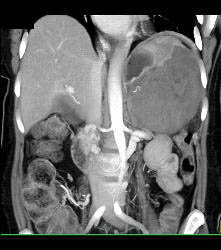

GIST Tumor